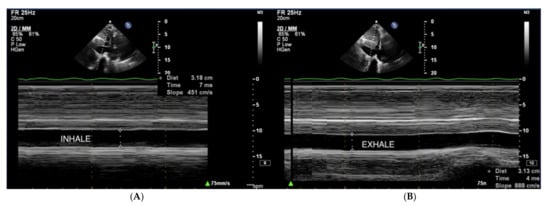

Right atrial pressure (RAP) is usually estimated based on the dimension and collapse rate of the inferior vena cava (IVC) in the subcostal view (Figure 11) [68]. The normal IVC width ranges between 15–21 mm, and IVC collapsibility on inspiration should exceed 50%. Moderately elevated pressure in RA exceeds 5 mmHg, and high pressure exceeds 10 mmHg [69].

Figure 11.

(A,B) IVC, no respiratory variability of IVC in the course of PAH. TTE, subcostal view. IVC: inferior vena cava; TTE: transthoracic echocardiography.